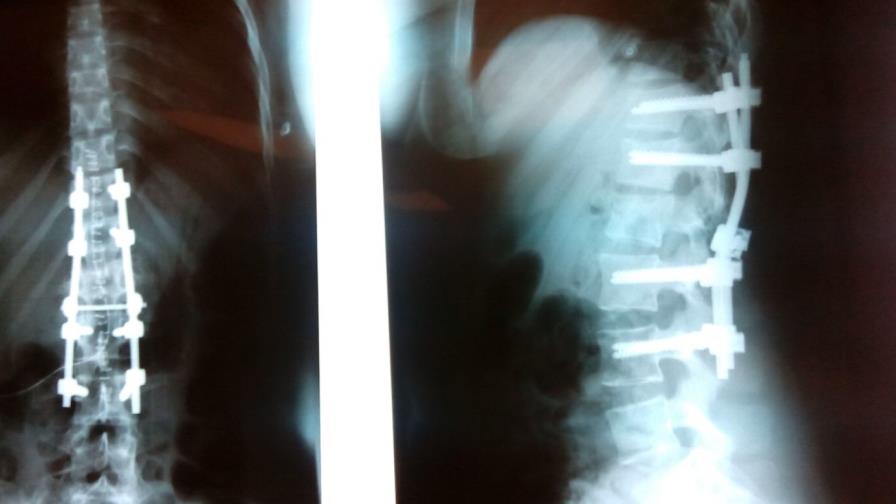

La joven Claudia Robles Barrot sufrió una fractura de aplastamiento en sus vértebras con ruptura ligamentosa en su columna producto de un aparatoso accidente de tránsito. Por el tipo de lesión, se temía que la misma causara una parálisis en sus piernas y le impidiera caminar de nuevo.

“Se le practicó una artródesis dorso-lumbar instrumentada con placas metálicas para fijar las vértebras. Es una cirugía compleja que requiere de gran precisión. Afortunadamente la paciente no presentó déficit neurológico ni pérdida sensitiva. Por tanto puede caminar con capacidad y función plena de sus extremidades inferiores” resaltó el doctor Del Villar.